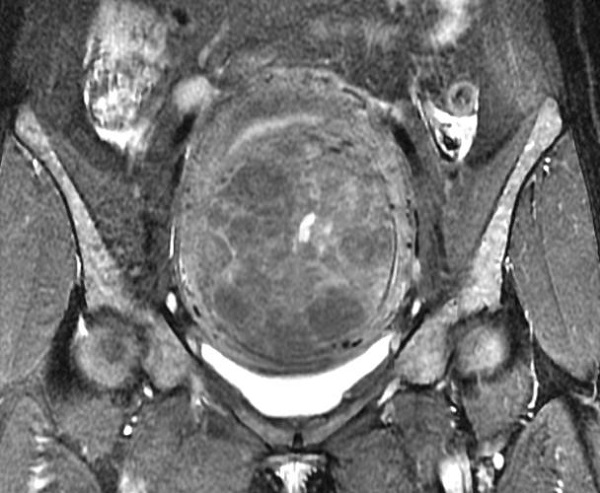

入院后给予抽血检查,随即检验科回报危急值:血红蛋白(46g/L)。立即给予输血治疗后,患者头晕、乏力等症状较前明显好转。完善盆腔磁共振,肌壁巨大子宫肌瘤(10.8cm×8.8cm×8.4cm)。经过制定详细手术计划后,排除手术禁忌,给予行“选择性子宫动脉栓塞术”。

(术前磁共振)